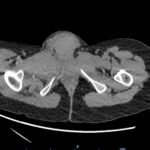

Non-obstetric vulvar hematoma is a rare but clinically important diagnosis in the emergency department for which there is no consensus on optimal diagnosis or management. We present a case of non-obstetric vulvar hematoma that occurred after minimal trauma in a young, otherwise healthy woman who presented with labial swelling after consensual digital penetration, initially managed conservatively but ultimately requiring surgical drainage. Although a rare presentation in the emergency department, prompt identification, diagnosis, and management of vulvar hematoma is crucial to appropriately treat complications including pain, hemodynamically significant hemorrhage, urinary obstruction, and soft tissue necrosis.

Vulvar hematoma, pelvic trauma, women’s health, CT (computed tomography) angiography.